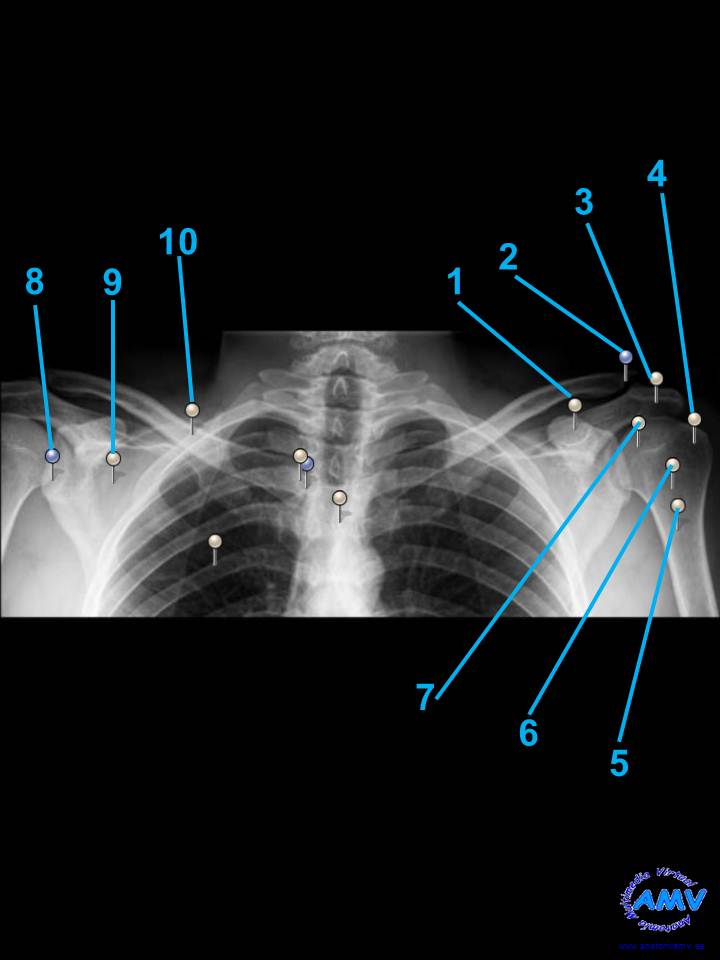

Radiografía Porción Superior del Tórax: Hombro

rx_ms_01.jpgIndique que estructura se señala con el número correspondiente:

El nº 1 señala .

El nº 2 señala .

El nº 3 señala .

El nº 4 señala .

El nº 5 señala .

El nº 6 señala .

El nº 7 señala .

El nº 8 señala .

El nº 9 señala .

El nº 10 señala .